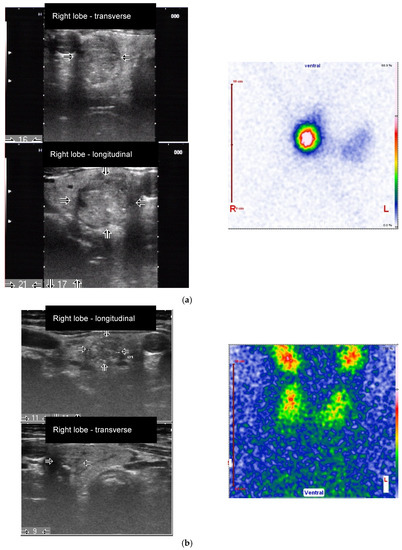

Figure 2.

Female patient (77 years old) with an autonomously functioning thyroid nodule (AFTN) (99mTc-pertechnetate image) in the right lower lobe (longitudinal and transverse images, nodule size: 16 × 17 × 21 mm, volume: 2.9 mL, arrows). (a) Before radioiodine therapy (RIT) (2016, TSH value < 0.1 mU/L, suppression with Levothyroxine) with 498 MBq (510 Gy). TIRADS classification: Kwak-TIRADS 4C (solid composition, microcalcifications, taller-than-wide shape, irregular margins); EU-TIRADS 5 (microcalcifications, taller-than-wide shape, irregular margins); (b) The same patient 7 months (follow-up 1, FU1) after RIT. The thyroid nodule size decreased to 9 × 11 × 11 mm (volume: 0.5 mL, arrows). Scintigraphy with 99mTc-pertechnetate shows a hypofunctioning area in the lower right lobe, which reflects a therapeutic response (TSH value 1.2 mU/L, no thyroid medications). TIRADS classification: Kwak-TIRADS 4C (solid composition, isoechoic/hypoechoic parts, microcalcifications and macrocalcification, taller-than-wide shape); EU-TIRADS 5 (microcalcifications, taller-than-wide shape); (c) The same patient 12 months after RIT (TSH value 1.2 mU/L, no thyroid medications). The thyroid nodule size at FU2 was 9 × 8 × 9 mm (volume: 0.3 mL, −90% reduction, arrows). TIRADS classification: Kwak-TIRADS 4C (solid composition, mildly hypoechoic, microcalcifications and macrocalcification); EU-TIRADS 5 (microcalcifications).